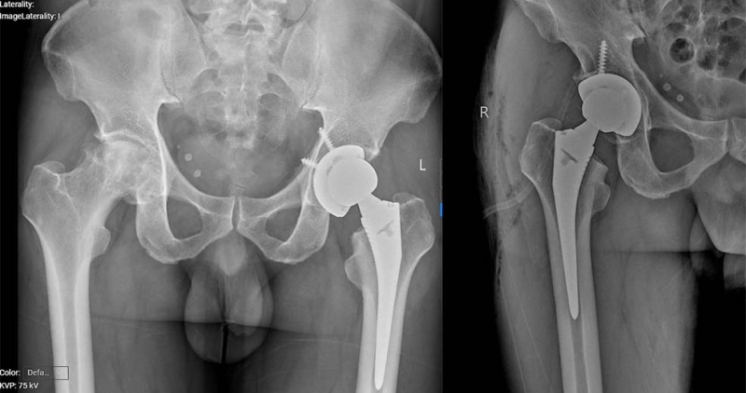

Mới đây, các bác sĩ Khoa Chấn thương Chỉnh hình, Bệnh viện Bãi Cháy đã phẫu thuật thay khớp háng cho bệnh nhân Vũ Kim H (40 tuổi, ở phường Móng Cái, tỉnh Quảng Ninh). Bệnh nhân có tiền sử hoại tử chỏm khớp háng hai bên, đã được phẫu thuật thay khớp háng trái cách đây 1 năm. Gần đây bệnh nhân xuất hiện đau và hạn chế vận động khớp háng phải.

Kết quả chụp xquang có hình ảnh đặc xương kèm tiêu xương không đều vùng chỏm xương đùi phải gây biến dạng xương đùi và hẹp không đều khe khớp háng phải. Các bác sĩ đã hội chẩn và đánh giá tình trạng hoại tử vô khuẩn chỏm xương đùi phải tiến triển và không còn khả năng bảo tồn. Người bệnh được chỉ định phẫu thuật thay toàn bộ khớp háng háng phải.

hoai-tu.png

Hình ảnh khớp phải trước và sau phẫu thuật - Ảnh BVCC

Ca phẫu thuật do BSCKII Vũ Quang Nghĩa, Trưởng Khoa Chấn thương chỉnh hình Bệnh viện Bãi Cháy thực hiện đã thành cắt bỏ tổn thương hoại tử, thay khớp háng bằng vật liệu nhân tạo phù hợp. Sau phẫu thuật 3 ngày, bệnh nhân phục hồi vận động tốt, có thể tập đi lại cùng dụng cụ tập.